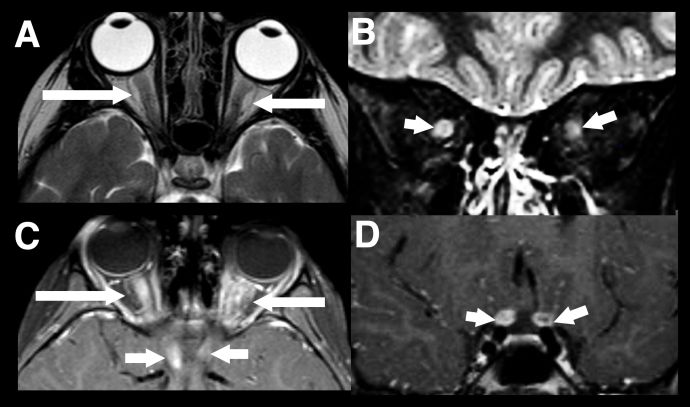

The second most common presentation of pediatric MOGAD is ON however in children radiographic features tend to be bilateral, longitudinally extensive (>1/2 the prechiasmatic optic nerve) an involve the anterior optic nerve which explains the higher incidence of disc swelling (Figure 3).[19] [20]

Figure 3 Longitudinally extensive optic neuritis. Typical imaging findings in a child with acute bilateral MOGAD optic neuritis. There is extensive marked swelling of the intraorbital optic nerve-sheath complexes bilaterally on T2-weighted images, particularly on the right (axial A, and coronal B, white arrows). Marked associated enhancement extending to the prechiasmatic segments of both nerves, are seen on post gadolinium T1-weighted images (axial C and coronal D, white arrows).